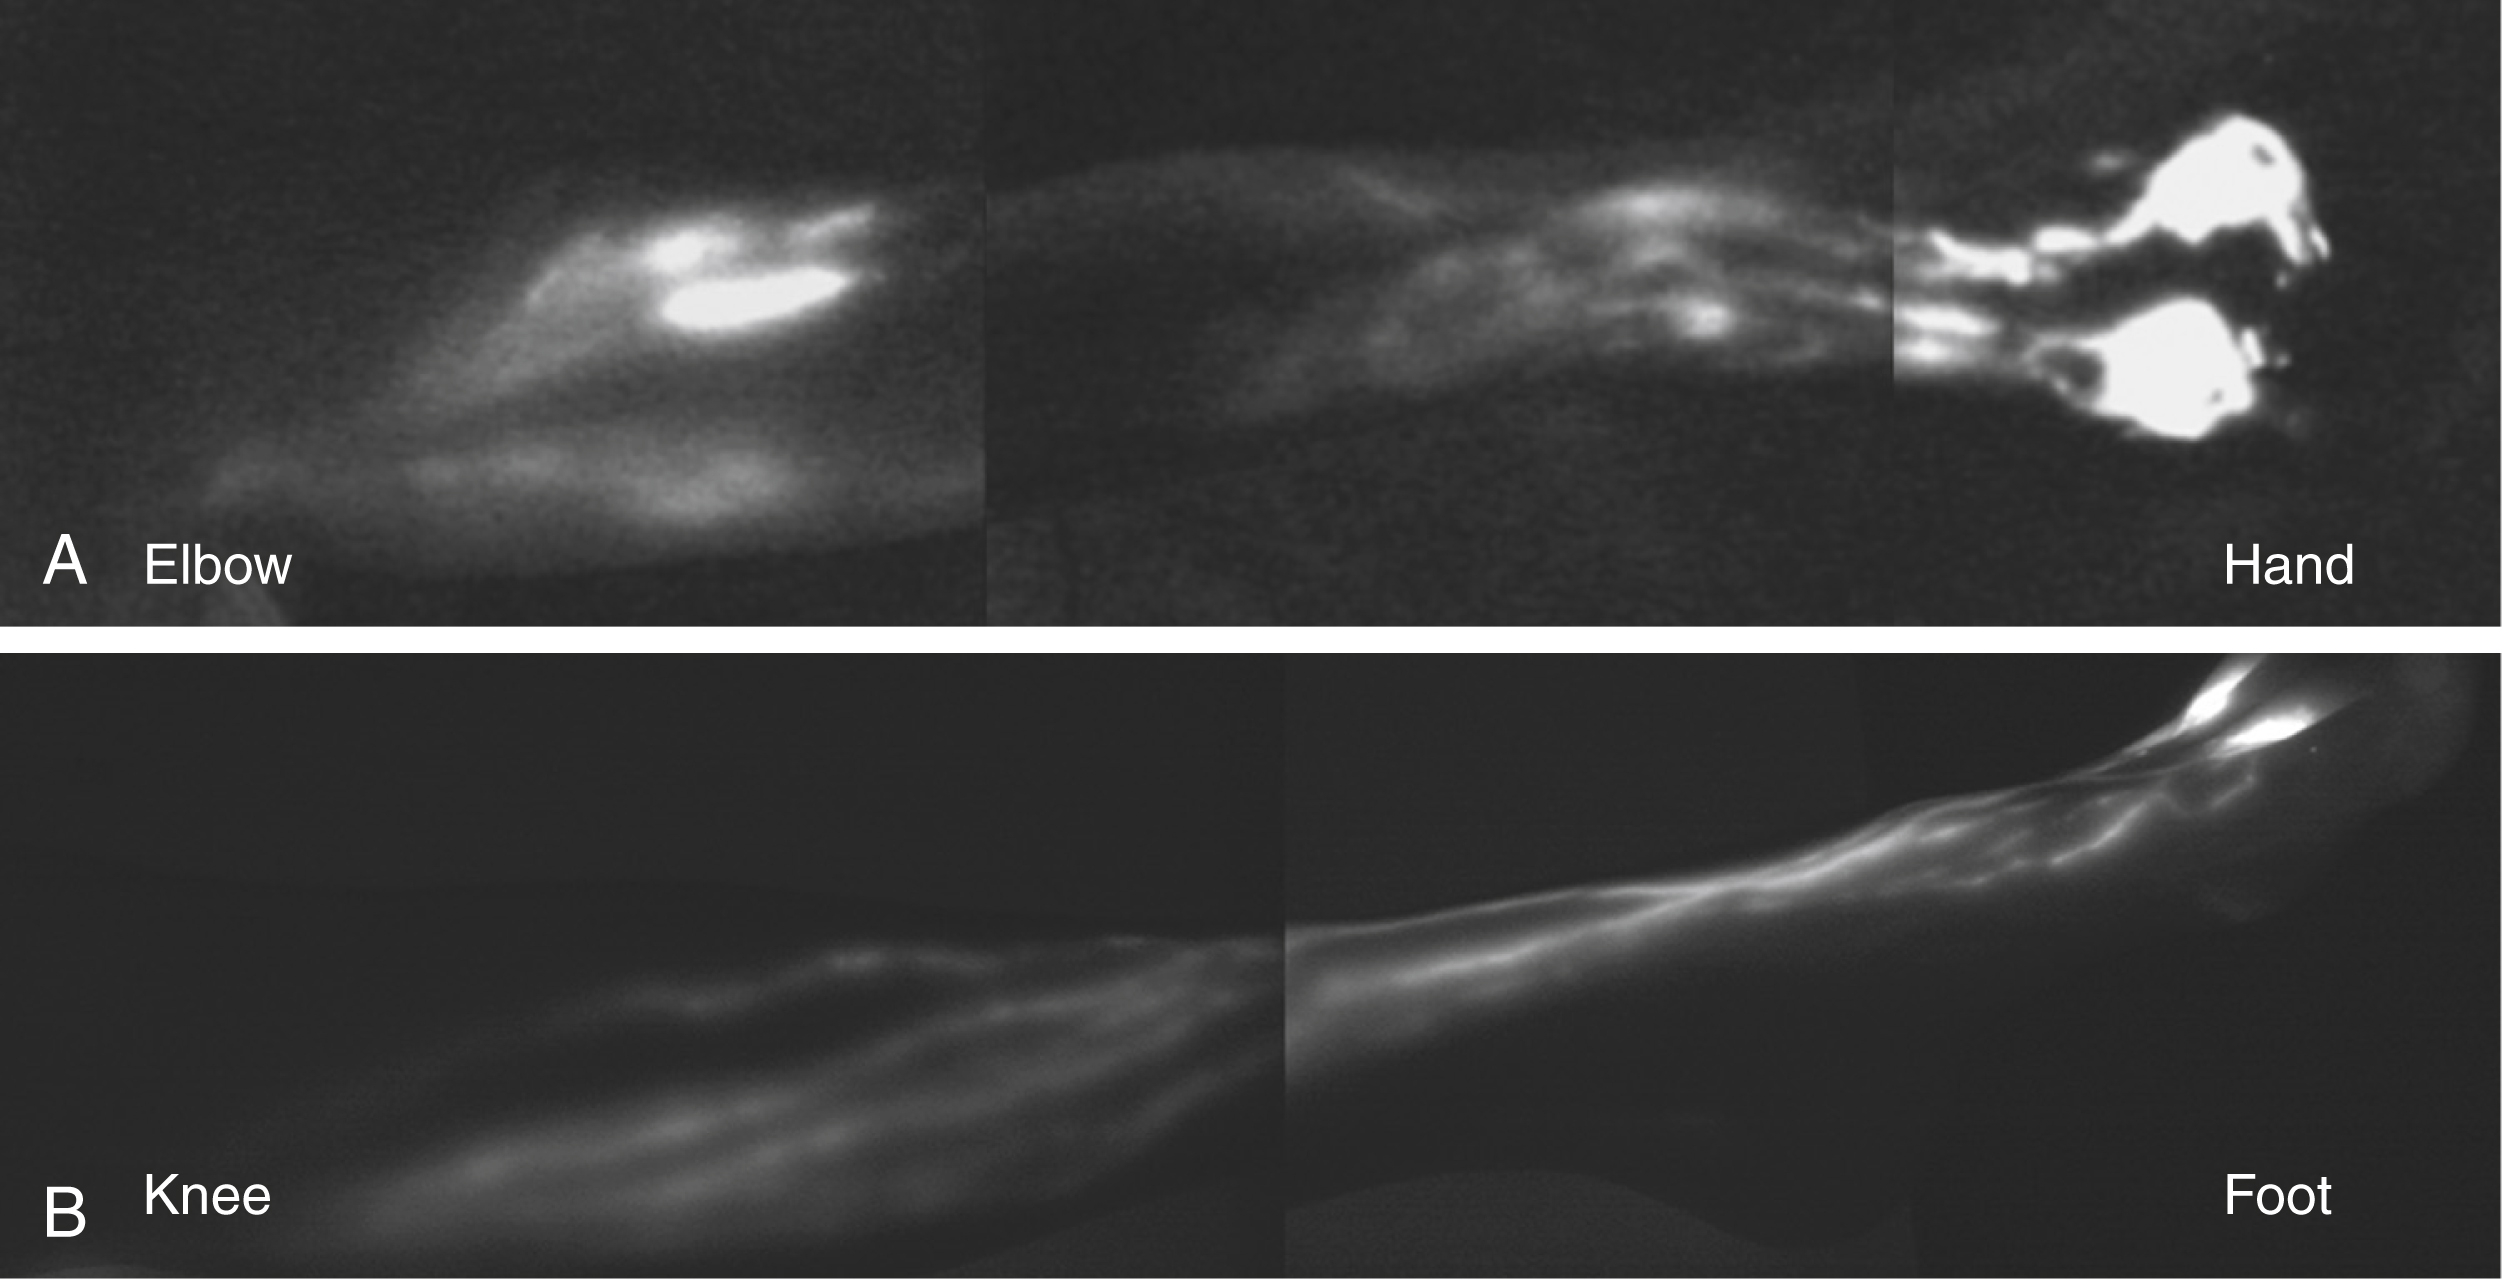

Fig. 44.2

(A) ICG anatomy of a healthy upper limb (volar view). Note dual drainage from the hand along radial and ulnar bundles of lymphatic channels and convergence of these pathways at the elbow. (B) ICG anatomy of a healthy lower limb (anteromedial view). Note drainage along the medial border of the leg.

In the lower extremity, lymphatics emerging from the toes and soles of the feet travel from the medial and anterior foot, ascending axially along the medial border of the leg (see Fig. 44.2 ). The vessels in the lower extremity range in size from 0.2 mm to 2.2mm in diameter and travel in the subcutaneous tissues. These lymphatic channels have a tortuous course and drain along the lesser saphenous vein, draining into the popliteal lymph nodes. Other collectors bypass the popliteal region and drain along the medial aspect of the thigh along the greater saphenous vein, draining into the inguinal lymph nodes.